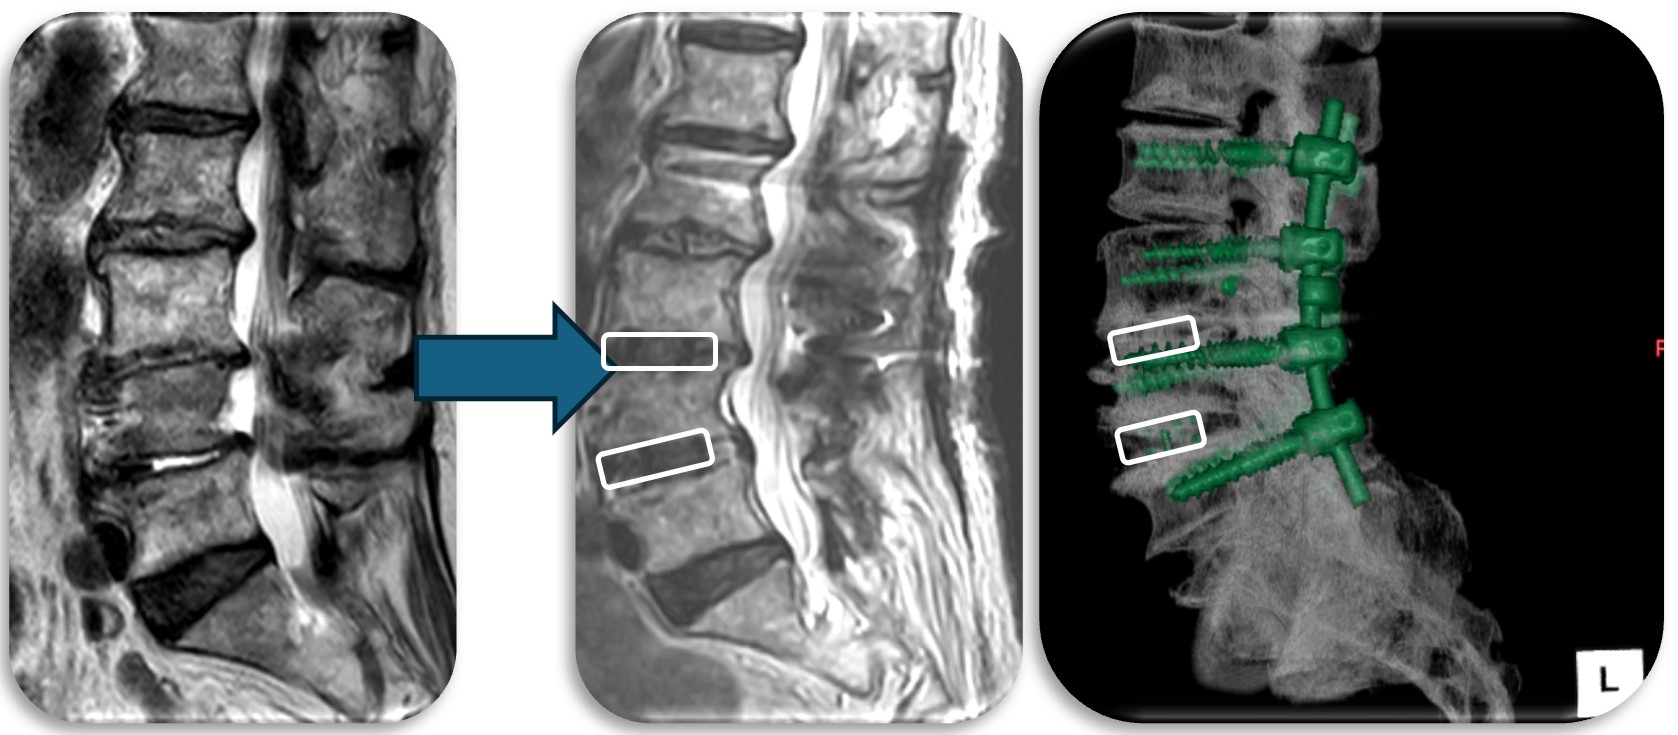

腰部の脊柱管狭窄症に対して、腰の側方から徐圧し、後方から固定術(OLIF)した症例です。椎間板が摩耗していたり、不安定性がある症例、後方からの手術歴があり再手術症例に適した手術方法です。狭小化した椎間板にスペーサーを挿入(白線)する事により、脊柱管の高さを正常な状態に戻し3次元的に狭窄を改善させます。

腰部の馬尾神経に発生した神経鞘腫の症例。脊髄腫瘍としては比較的多く割合を占める神経鞘腫は良性腫瘍であり、基本的には全摘出が可能で予後も良好です。この症例も坐骨神経痛と間欠跛行という馬尾障害の症状を呈していましたが、術後は改善し再発も認めておりません。